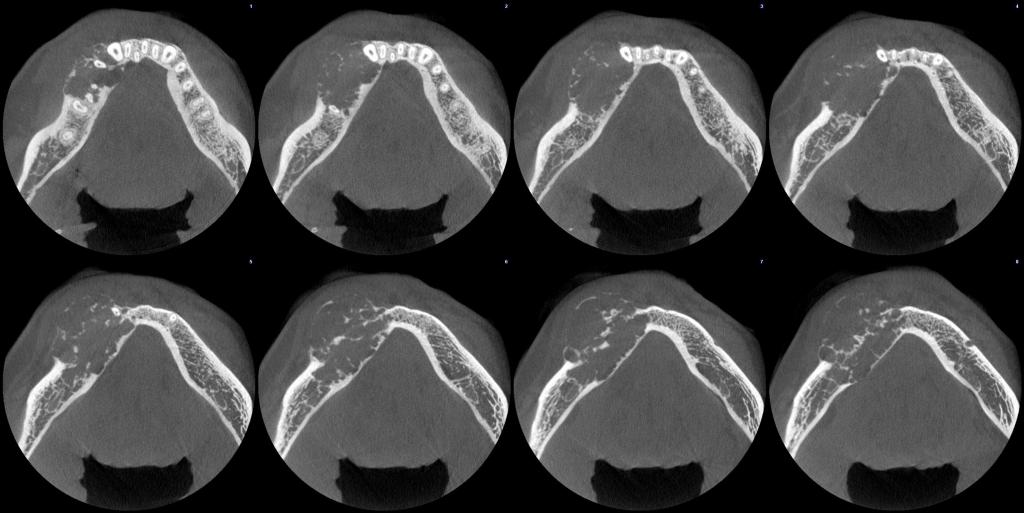

常规开展:数字化根尖片/横断牙合片、数字化口腔曲面体层片、头影测量侧位/正位片、手腕骨片、颅颌面CBCT、牙齿CBCT的检查以及涎腺造影、窦道 瘘管造影。

颅颌面CBCT